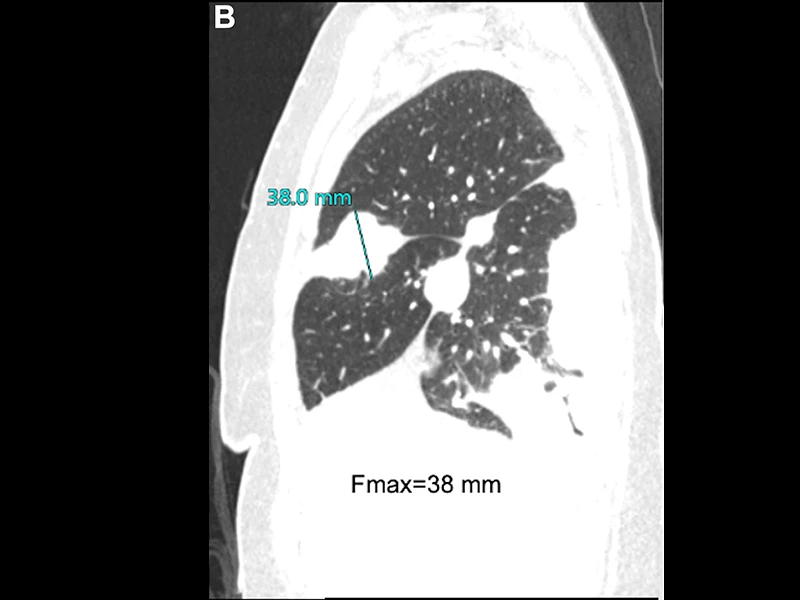

Sagittal image revealing fissure involvement by tumor; maximal fissure thickness Fmax=38 mm